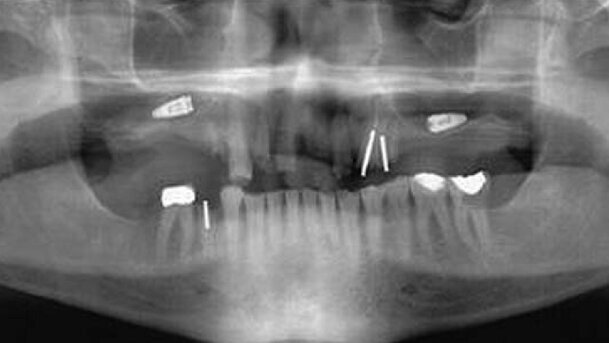

Une recherche dans la littérature et sur Internet, a fait ressortir plusieurs publications concernant ces complications, et notamment des fractures d’implants (Fig. 1), des empiètements sur les dents adjacentes (Fig. 2), des perforations de la corticale linguale (Fig. 3), des perforations des cavités sinusales (Fig. 4) et des migrations d’implants dans les sinus maxillaire (Fig. 5).

La prise en charge clinique associée à certaines de ces complications est parfois difficile et considérée comme très invasive. Par conséquent, bien que l’on n’ait pas déterminé le rapport quantitatif entre les résultats très positifs du traitement implantaire dentaire et l’imagerie dentaire CBCT, et que l’on soit en attente des conclusions de vastes essais cliniques prospectifs, je crois fortement que l’utilisation de l’imagerie dentaire 3D et CBCT se présente comme une technique fiable du point de vue du principe de précaution, si l’on en juge par toute une série d’études cliniques préliminaires et d’études de cas menées récemment.

Je suis aussi convaincu que la prise d’images 3D et CBCT avant une pose d’implants dentaires, peut permettre de contourner les complications susmentionnées.